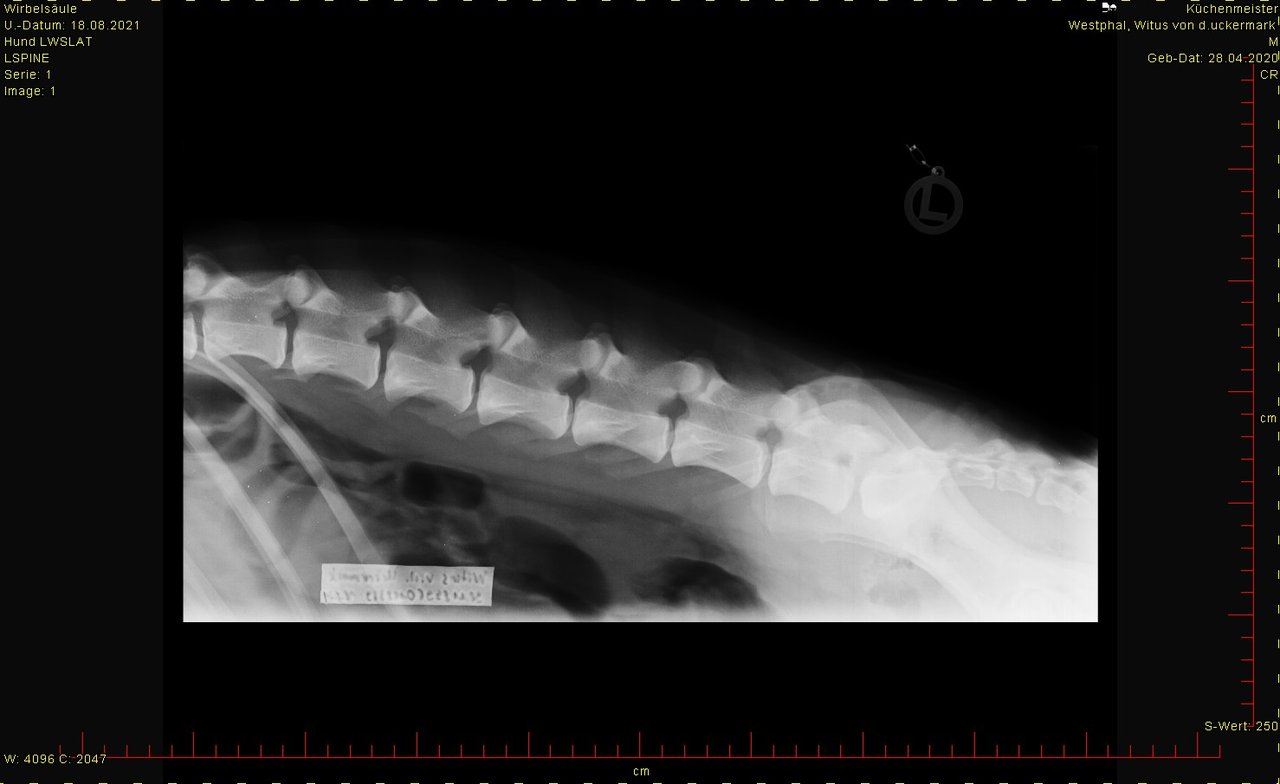

ED hat er nicht, LÜW sah auch ok aus.

Bei den Ellenbogen traue ich mir keine Bewertung zu, finde aber, dass Hüfte und Rücken okay sind